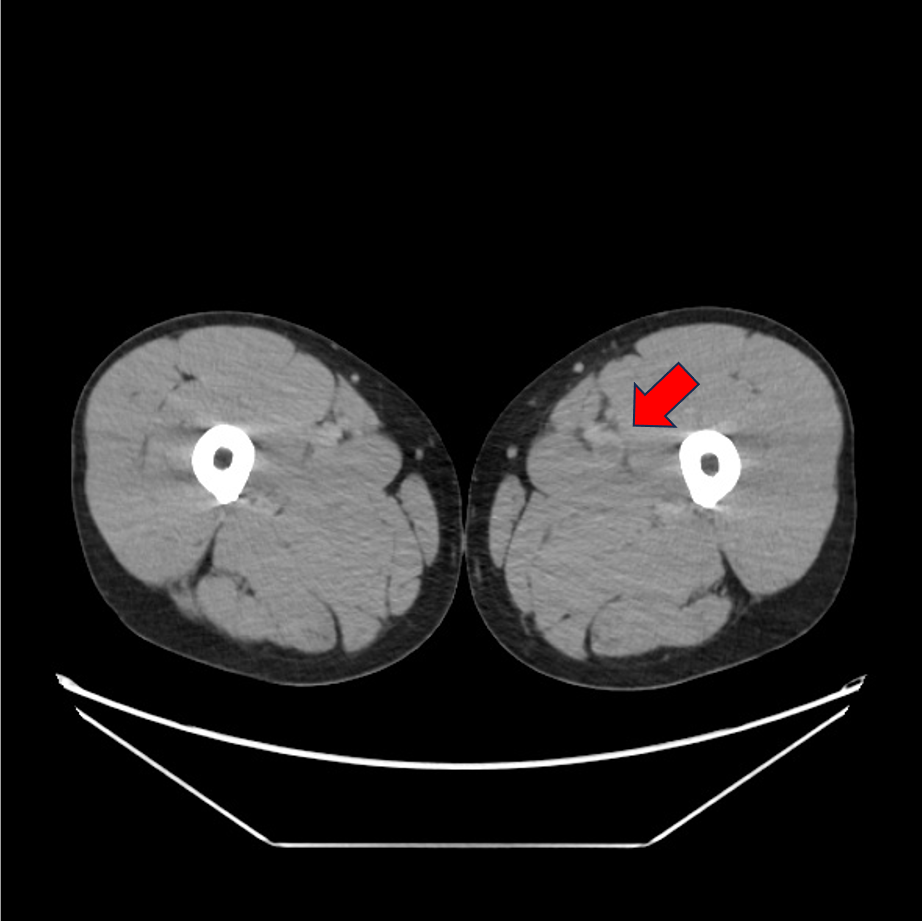

症例は40歳代男性。左下腿の浮腫、疼痛と労作時息切れを認め、血液検査にて血清D-dimerが高値であったため、肺血栓塞栓症の精査目的に造影CTが施行された。両側肺動脈と両側下肢静脈に造影欠損域を認め、それぞれ肺血栓塞栓症、深部静脈血栓症が考えられた。その後、抗凝固療法が施行されて血栓は縮小し、退院となった。

CT技術や撮像プロトコル設定について